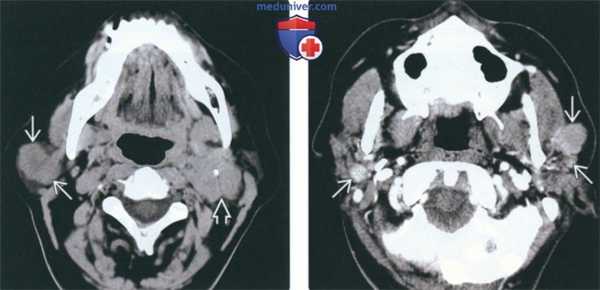

(Слева) На аксиальной КТ без КУ в правой околоушной железе визуализируется большая опухоль с четкими краями - гематогенный метастаз рака легкого. Визуализируется также крупный регионарный метастаз в контралатеральном лимфоузле II уровня; справа не выявлено признаков шейной лимфаденопа тип.

(Справа) На аксиальной КТ с КУ в обеих околоушных железах у пациентки с известным раком молочной железы визуализируются множественные опухоли (гематогенные метастазы) с четкими краями, равномерно накапливающие контраст.